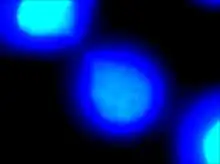

| DAPI staining allows for visualization of deoxyribonucleic acid portions of the two daughter cells. The thin “string-like” DNA connecting them is defined as a chromatin bridge. | |

Chromatin bridge is a mitotic occurrence that forms when telomeres of sister chromatids fuse together and fail to completely segregate into their respective daughter cells. Because this event is most prevalent during anaphase, the term anaphase bridge is often used as a substitute. After the formation of individual daughter cells, the DNA bridge connecting homologous chromosomes remains fixed. As the daughter cells exit mitosis and re-enter interphase, the chromatin bridge becomes known as an interphase bridge. These phenomena are usually visualized using the laboratory techniques of staining and fluorescence microscopy.[1][2]

Chromatin bridges can be viewed utilizing a laboratory technique known as fluorescence microscopy. Fluorescence is the process that involves excitation of a fluorophore (a molecule with the ability to emit fluorescent light in the visible light spectrum) using ultraviolet light. After the fluorophore becomes chemically excited by the presence of UV light, it emits visible light at a specific wavelength, producing different colors. Fluorophores may be added as a molecular tag to different portions of a cell. DAPI is a fluorophore that specifically binds to DNA and fluoresces blue. In addition, immunofluorescence may be used as a laboratory technique to tag cells with specific fluorophores using antibodies, immune proteins created by B lymphocytes. Antibodies are utilized by the immune system in the identification and binding of foreign substances. Tubulin is a monomer of microtubules that compose the cellular cytoskeleton. The antibody anti-tubulin specifically binds to these tubulin monomeric subunits. A fluorophore can be chemically attached to the anti-tubulin antibody, which then fluoresces green. Numerous antibodies may bind to microtubules in order to amplify the fluorescent signal. Fluorescence microscopy allows for the observation of different components of the cell against a dark background for high intensity and specificity.

Chromatin bridges are easiest and most readily visible when observing chromosomes stained with DAPI. DNA bridges appear to be a blue, “string-like” connection between two separated daughter cells. This effect is created when sticky ends of chromosomes remain connected to one another, even after mitosis. A chromatin bridge may also be observed using indirect immunofluorescence, in which anti-tubulin emits a green coloration when bound to microtubules in the presence of UV light. Because microtubules maintain the positions of the chromosomes during mitosis, they appear to be densely pinched between the two dividing, daughter cells. Chromatin bridges can be difficult to locate utilizing fluorescence microscopy, as this phenomenon is not incredibly abundant and tend to appear faint against the dark background.